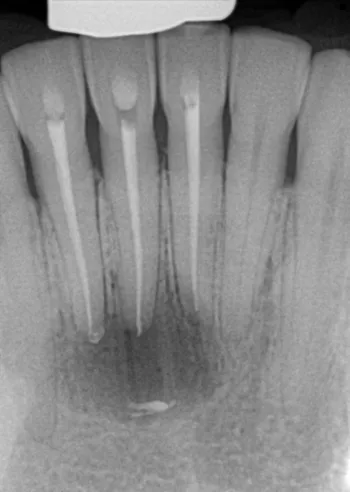

Before

After

Patient is a 64 year old female. Recommended treatment for root canal on teeth 7 and 9 and retreatment of 10. The first x-ray is dated 6-23-23, procedure was completed 7-7-23. She was seen for 6 months follow up visit 1-10-24 and has had some tenderness and swelling recommended CBCT for comparison. Dr. Malavia did recommend Apicoetomy for teeth #9 and 10, surgery was done 2-20-24. The final x-ray is dated 3-7-25